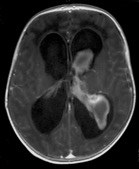

imagerie

- l’échographie, couplée au Doppler est l’examen de référence, non invasif, fait au lit du patient et répétable, il permet de diagnostiquer des lésions cérébrales associées et de suivre l’évolution de la taille ventriculaire et du retentissement hémodynamique

Echo-Doppler montrant une HTIC sévère avec reverse-flow (à gauche), et correction hémodynamique après ponction soustractrice (à droite) - l’IRM est importante à visée pronostique